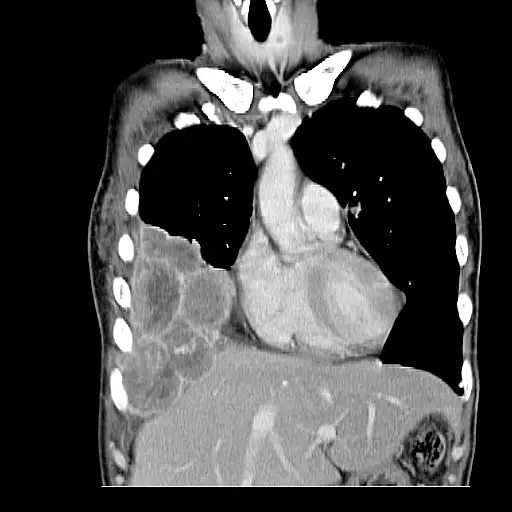

有關下圖的敘述,下列何者錯誤?

A為有靜脈注射含碘顯影劑之冠狀重組之電腦斷層攝影圖

B有呈現心室中隔

C有呈現下行主動脈

D右下胸有腫塊,有呈現肝靜脈

本題考驗冠狀重組CT影像下,對心血管結構(心室中隔、主動脈)、肝臟血管及病灶之辨識。

從冠狀重組CT上,可見:

- 心臟位於胸腔中央偏上,左右心室輪廓分明,心室中隔界線清楚可辨。

- 兩肺呈低密度影,右側下肺野有一不規則、高於肺組織的軟組織密度團塊(疑似腫塊)。

- 影像中下方為橫膈膜,橫膈膜下顯示肝實質,肝內可見數條放射狀、連接肝臟中心的大血管(肝靜脈)。

- 胸椎旁典型的下行主動脈(環狀高密度管狀影)在本圖並未明顯顯示。

選項A 為「有靜脈注射含碘顯影劑之冠狀重組之電腦斷層攝影圖」。

影像中血管及肝靜脈皆呈高密度,符合靜脈注射顯影劑後的表現;此外切面乃從前到後的冠狀重建影像,符合描述 (quizgecko.com)。 -

選項B 「有呈現心室中隔」。

冠狀面CT可直接觀察左右心室分界的中隔線影,本圖中心心室中隔清晰可見 ([digital-health-scholars.github.io](https://digital-health-scholars.github.io/gha-public/regions/thorax?utm_source=op